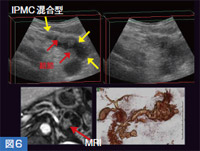

図6はIPMC( 膵管内乳頭粘液性腺癌)混合型の症例で,主膵管と分枝膵管の両方に結節が見られる。ノイズが多く嚢胞部分が不明瞭だが,ソナゾイド造影を行うと投与後20 〜 30秒程度で膵実質が最も強く濃染され,その後コントラストに優れた3Dイメージが得られた。これをVR表示して内腔面を観察すると,大きな結節以外にもたくさんの凹凸が見られた(図7)。IPMCは良悪性境界病変も多いため,嚢胞内腔面の凹凸が良好に認識できることは,非常に大きなメリットと考えている。当院では,ERCPや切除手術などで確定診断がついた15mm以上の嚢胞性病変を持つ77症例について,嚢胞の内腔面の状態を3Dイメージのパターンで分類した。その結果,内腔面が平滑なT〜V型には悪性病変は1例も含まれていなかった。3Dイメージを用いることで病変の客観的な評価が可能になり,良悪性の鑑別にも役立つと期待している。

図6